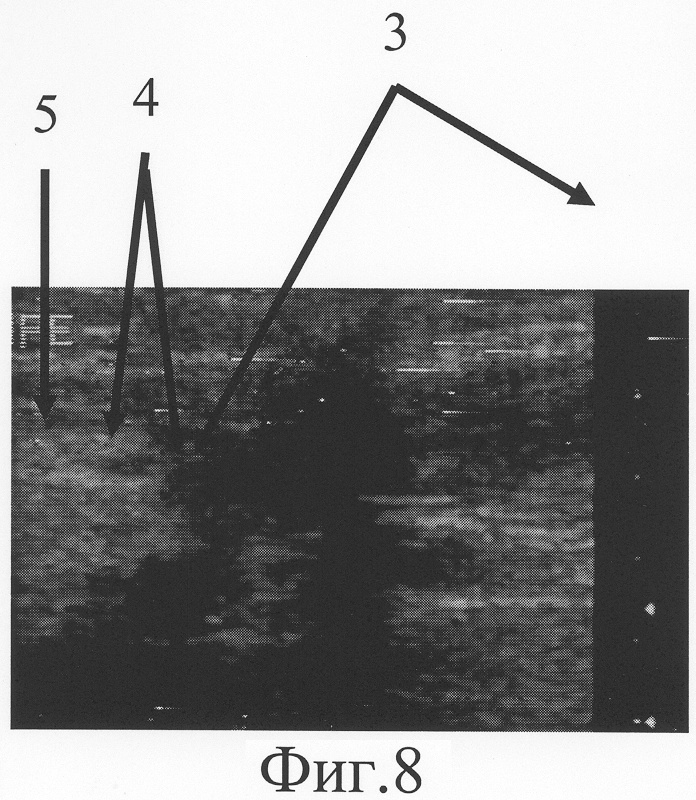

На фиг.8 представлена сонограмма больного П., 51 года, с застарелым повреждением локтевого нерва в средней трети правого предплечья (дистальный фрагмент нерва).

При ультрасонографическом исследовании (фиг.7, 8) установлено, что локтевой нерв поврежден на уровне средней трети правого предплечья. Его проксимальный фрагмент (фиг.7-1) заканчивается невромой (фиг.7-2), линейный размер которой составляет 4 мм. Дистальный фрагмент (фиг.8-5) патологически измененен на протяжении 5 мм. (фиг.8-4). Диастаз между невромой и дистальным фрагментом равен 47 мм (фиг.8-3, фиг.8-3). Размер участка срединного нерва, подлежащего возмещению, составляет сумму линейного размера невромы проксимального фрагмента по линии продольной оси нервного ствола, протяженности диастаза между невромой и дистальным фрагментом, линейного размера патологически изменененного дистального фрагмента и равен 56 мм.